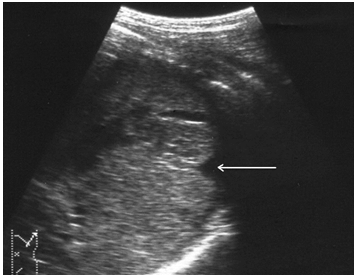

В ряде случаев выявляется несколько эхонегативных зон, расположенных в непосредственной близости. Практически в половине наблюдений в травматической полости визуализируются эхопозитивные фрагменты различных размеров и формы, представляющим собой сгустки крови и тканевые секвестры (рис. 5, а, б). Подобная точка зрения подтверждается их обратным развитием с образованием мелкодисперсной взвеси осадка в содержимом полости по истечении 7–10-ти суток после травмы.

Эхографически эволюция внутриорганных гематом характеризуется прогрессивным сокращением объема травматической полости, снижением четкости контуров, неоднородным повышением эхогенности ее содержимого за счет заполнения множественными точечными структурами, соответствующими по эхогенности паренхиме селезенки (рис. 6).

Рис. 5. Эхограмма подкапсульного разрыва селезенки: а – сгусток крови в посттравматической полости; б – тканевый секвестр в посттравматической полости.

Рис. 6.

Репаративная регенерация при травме селезенки. Точечные эхосигналы в посттравматической полости указаны стрелками.

Необходимо отметить, что определенные изменения претерпевает также форма травматической полости, утрачивая характерный звездчатый контур и приобретая округлые очертания. Длительность течения репаративно-регенеративных процессов при подкапсульных разрывах селезенки определяется прежде всего размерами (объемом) травматической полости и достигает 4-х месяцев, по истечении которых констатируется полная нормализация акустической плотности и эхоструктуры паренхимы органа. Результаты цветового допплеровского картирования также свидетельствуют о полном восстановлении кровотока.